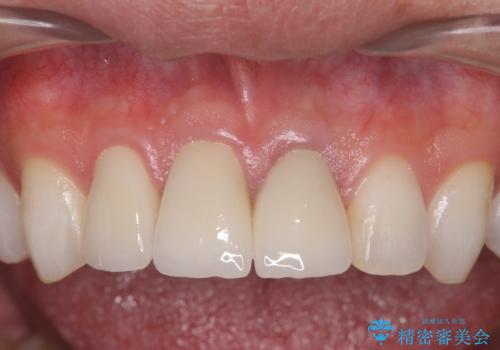

歯の挺出を行ったことで歯ぐきの腫れも改善され、安定した歯周環境下でのセラミッククラウン治療を行うことができました。

・歯の変色 →ジルコニアクラウンの製作

- 50.6万円(ジルコニアクラウン×3・仮歯×3・歯の挺出&歯周外科)費用は治療当時の料金となります